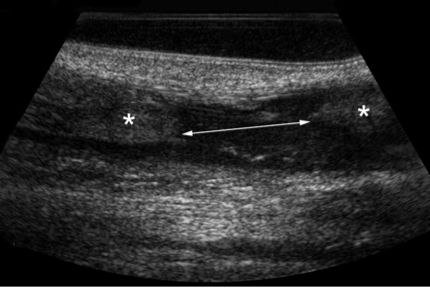

Patient de 22 ans, vient vous voir suite à une douleur soudaine après un fractionné piste. Le patient dit avoir

entendu comme un coup de fusil a eu une douleur vive au talon d’Achille.

Le patient boite et a du mal à poser le pied. Que voyez-vous à l’imagerie ?

Rupture complète du tendon calcanéen.

Échographie en coupe sagittale permettant de visualiser la solution de continuité hypoéchogène (↔) entre les deux fragments tendineux (*).